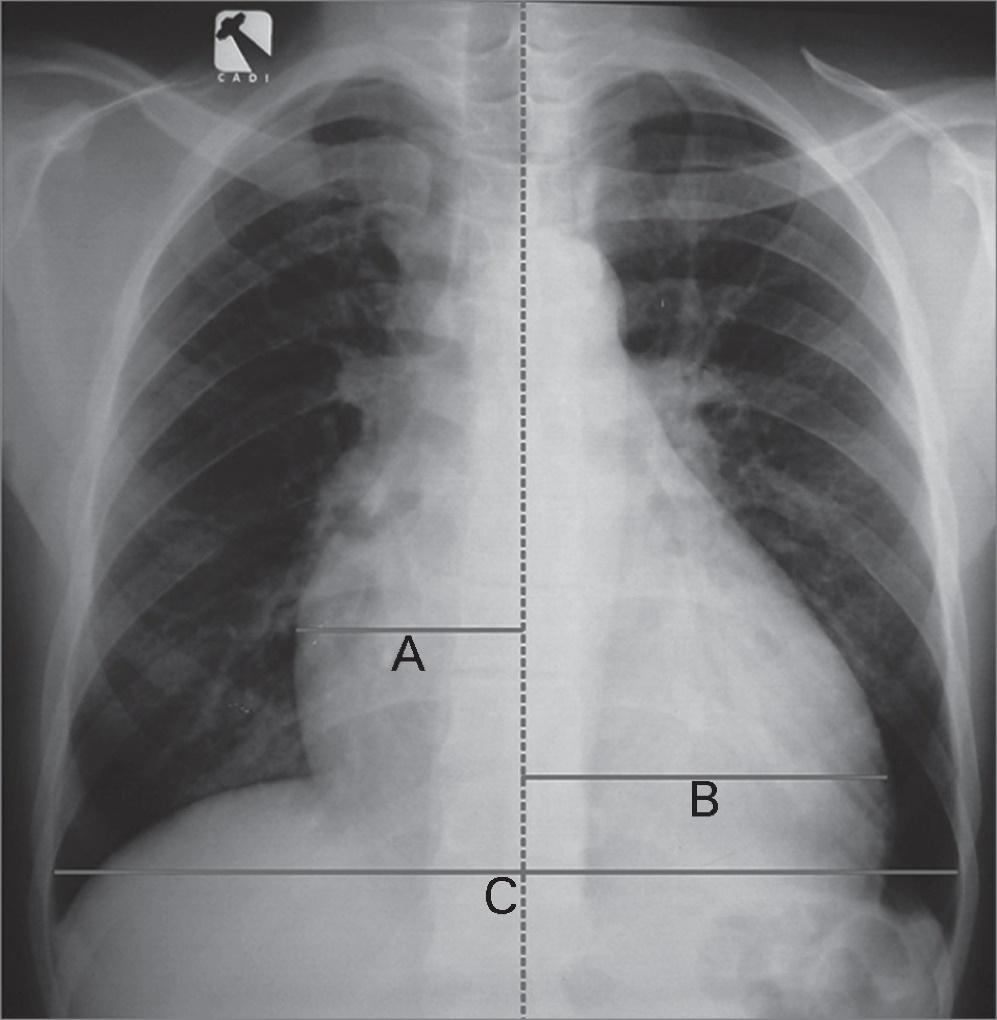

O raio-X de tórax sempre deve ser solicitado. E o aumento do índice cardiotorácico indica sobrecarga de ventrículo esquerdo, e está associado a insuficiência aórtica.